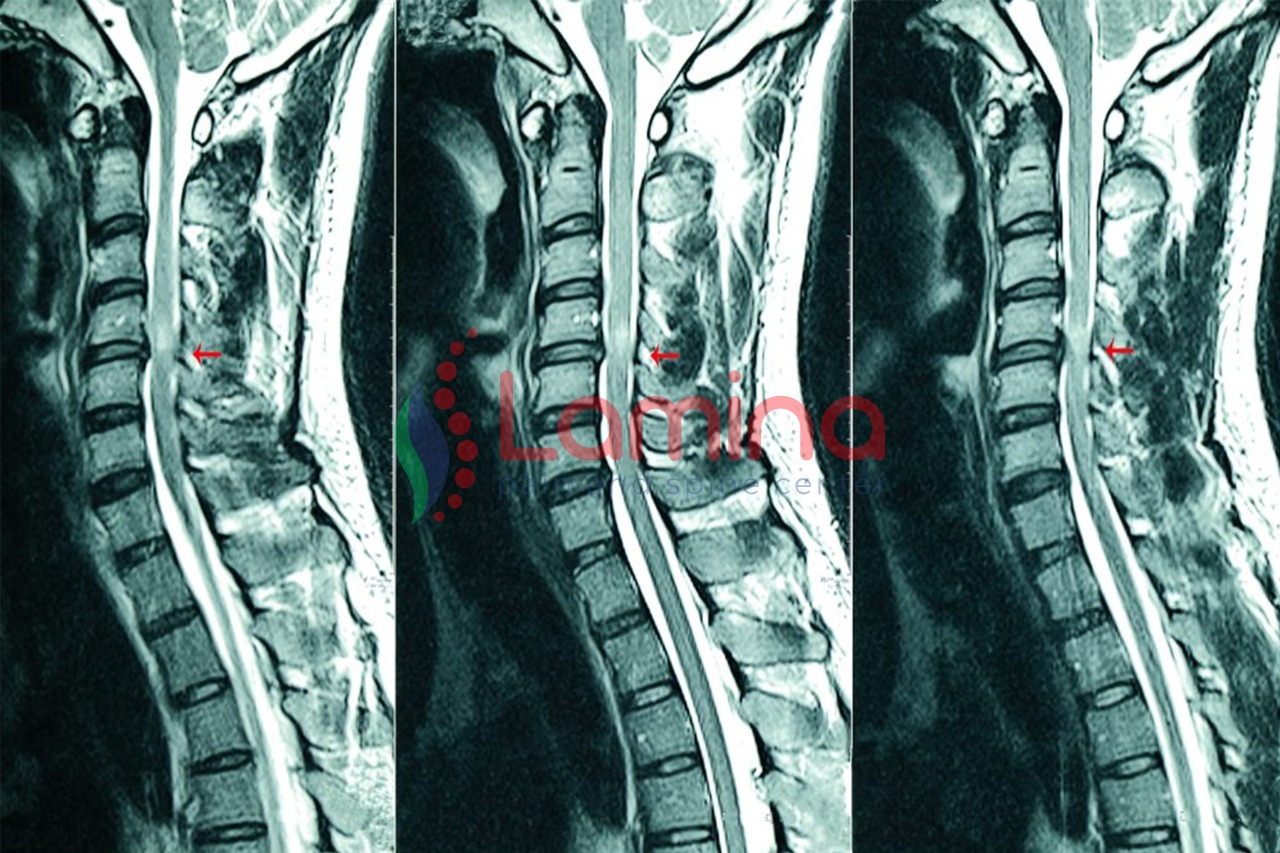

Saraf kejepit atau  dalam istilah medis  hernia nukleus pulposus (HNP), merupakan kondisi ketika  bantalan ruas tulang belakang terjadi pergeseran sehingga membuat syaraf tulang belakang tertekan.

Lebih lanjut, HNP juga bisa terjadi pada bagian leher (HNP servikal/ saraf terjepit leher) meskipun kasusnya tidak sebanyak saraf terjepit pinggang. J Pasien HNP servikal biasanya akan merasakan gejala nyeri pada  bagian bahu, leher, dan lengan.